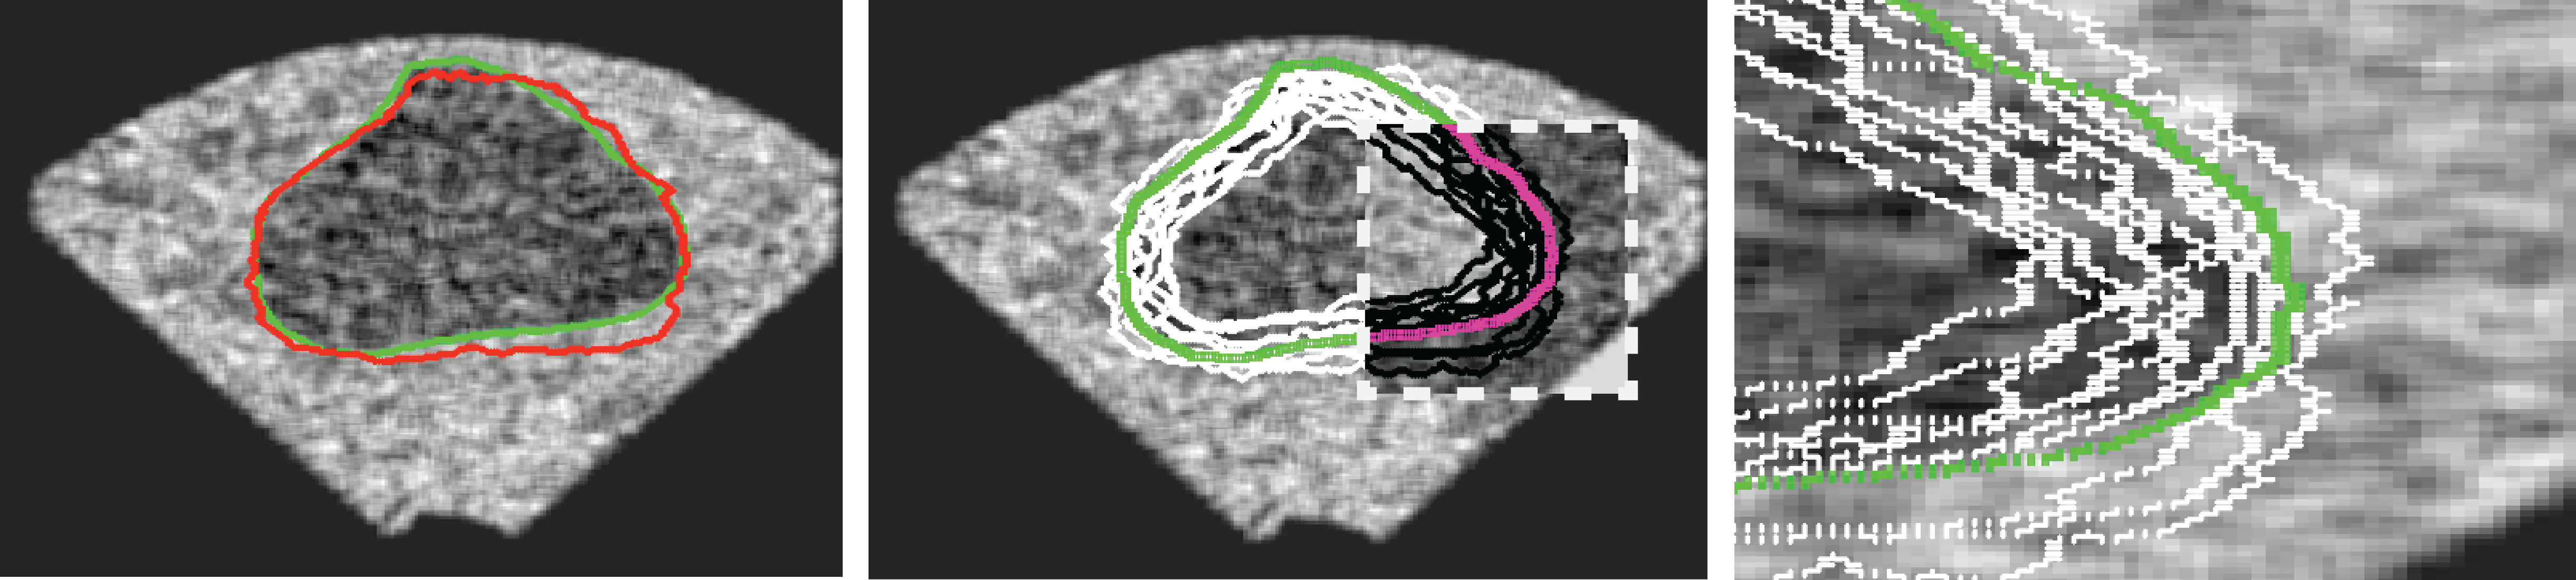

We generated 500 images from their corresponding gold-standard images. Furthermore, we generated 20 different segments for each image, assuming that there were 20 users. Figure 4 shows three examples of real and synthetic TRUS images. One should bear in mind that the purpose here was not to simulate the images realistically, but rather to have a base from which to generate variable segments from a perfect segment. Figure 5 shows an example of the gold segments and simulated user contours. The variability, coupled with the gold segment, is what is needed to validate our approach.

Sample images are depicted in Figure 6 (top row). Generally, one assumes that prostate segmentation is a relatively easy task. However, the variability of such segmentation remains considerable, and this is conspicuous in Figure 6 (bottom row).